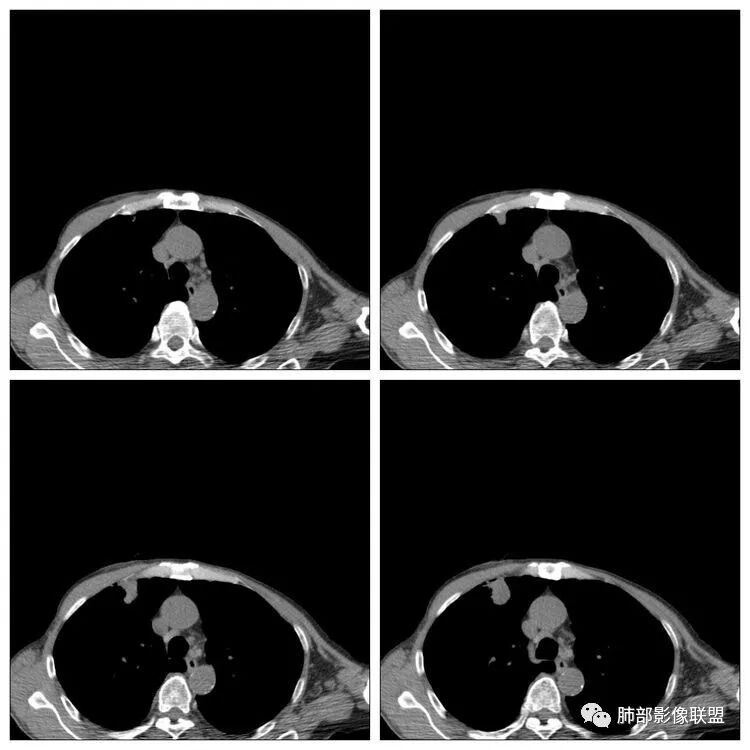

患者男性,70岁;既往有高血压病病史,还有冠心病病史;不嗜烟酒;因头昏入院,查胃镜病理提示鳞状细胞癌,胸部CT提示右上肺占位性病变。

南边:患者男性,70岁;既往有高血压病病史,还有冠心病病史;不嗜烟酒;因头昏入院,查胃镜病理提示鳞状细胞癌,胸部CT提示右上肺占位性病变。

老年男性,有胃癌可惜没增强南边:常规:1、转移瘤2、肺癌3、炎性病变为啥考虑炎性?小赵:局部边缘平直南边:

南边:我们担心的,它是在一个转移的基础上,还有合并有炎症,担心这个隐藏在其中,因为它这个边缘,是不是很清楚光滑哈,但是我们都记得转移瘤,他很多都是边界清楚光滑的,对不对。就觉得,中间这个结节跟周围的病灶好像形态、密度各方面都不一致的。我就担心它是一个转移瘤,合并感染,周围炎性病变,中间是一个转移瘤结节这样的就麻烦了。所以常规我会建议他抗炎治疗后复查。看看那个残留的病灶怎么样,本质是如何,要么穿刺,这个病变我只能说炎性它一定有。南边:里面那个病灶就是那个类圆形的病灶,跟外面那个肯定是不一致的,就那个类圆形病灶,到底是一个转移瘤,还是单纯炎性病变的部分。目前这个片只能等复查,毕竟边缘是膨隆的,而且我们刚才也说了,转移瘤的特点,如果血道转移,他就是边界清晰光滑的。所以成这样,有这么巧的话你就没办法。南边:关于血管纠集,它就这样的,炎性病变也可以这样表现,牵拉过来,原理不同,但是影像表现已经表现很类似,我们往往关注支气管。支气管进入这个病灶的表面的时候是否堵塞,或者血管,进入这个病灶里面,是否走行是否自然;这些这些可能价值大一些,但是他是不是一个恶性征象,是;但是它的比例就是在炎性病变也不低。原发呢,不敢说没有,但是一般来说几率偏低吧。